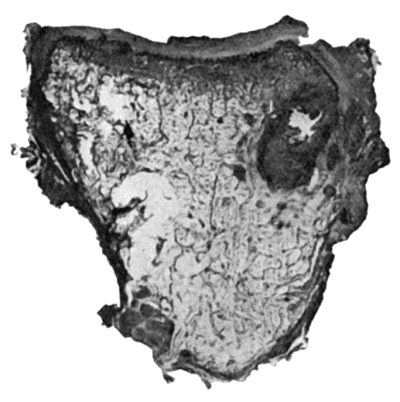

114.Section through Gouty Bursa 428